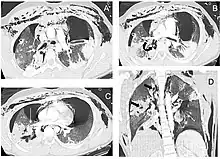

| Reconstruction of the trachea and bronchi with x-ray computed tomography showing disruption of the right main bronchus with abnormal lucency (arrow)[1] | |

Chest x-ray is the initial imaging technique used to diagnose TBI.[17] The film may not have any signs in an otherwise asymptomatic patient.[15] Indications of TBI seen on radiographs include deformity in the trachea or a defect in the tracheal wall.[17] Radiography may also show cervical emphysema, air in the tissues of the neck.[2] X-rays may also show accompanying injuries and signs such as fractures and subcutaneous emphysema.[2] If subcutaneous emphysema occurs and the hyoid bone appears in an X-ray to be sitting unusually high in the throat, it may be an indication that the trachea has been severed.[4] TBI is also suspected if an endotracheal tube appears in an X-ray to be out of place, or if its cuff appears to be more full than normal or to protrude through a tear in the airway.[17] If a bronchus is torn all the way around, the lung may collapse outward toward the chest wall (rather than inward, as it usually does in pneumothorax) because it loses the attachment to the bronchus which normally holds it toward the center.[6] In a person lying face-up, the lung collapses toward the diaphragm and the back.[23] This sign, described in 1969, is called fallen lung sign and is pathognomonic of TBI (that is, it is diagnostic for TBI because it does not occur in other conditions); however it occurs only rarely.[6] In as many as one in five cases, people with blunt trauma and TBI have no signs of the injury on chest X-ray.[23] CT scanning detects over 90% of TBI resulting from blunt trauma,[3] but neither X-ray nor CT are a replacement for bronchoscopy.[6]